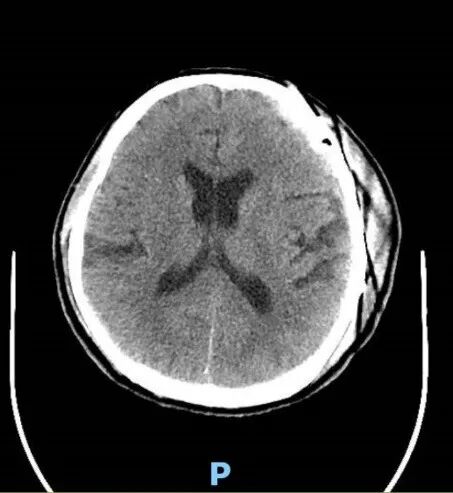

术后,在神经外科五病区全体医护人员的精心照料下,患者恢复情况良好,身体状态一天天好转。当术后复查 CT 显示手术效果理想,病理报告明确诊断为良性脑膜瘤的那一刻,患者及家属心中的大石终于彻底落地。

术后患者复查CT及病理结果